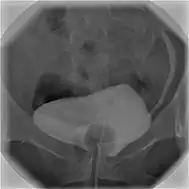

Cystographie

La cystographie est une radiographie qui permet d'explorer les parois de la vessie et de l'urètre. Cet examen utilise des rayons X et un produit à base d'iode. Ce dernier est le plus souvent injecté directement dans la vessie à l'aide d'une sonde passant par l'urèthre (cystographie rétrograde), plus rarement en piquant dans la vessie à travers la paroi abdominale (cystographie suspubienne)[1].

Les clichés sont réalisés en deux temps. D'abord pendant le remplissage de la vessie, puis dans un second temps, pour étudier les parois de l'urèthre, des clichés seront pris pendant que le patient urine[1]. La cystographie est complémentaire de l'échographie permettant de voir des anomalies qui échappent à cette dernière[3],[4]. On appelle cystogramme les images obtenues avec la cystographie.